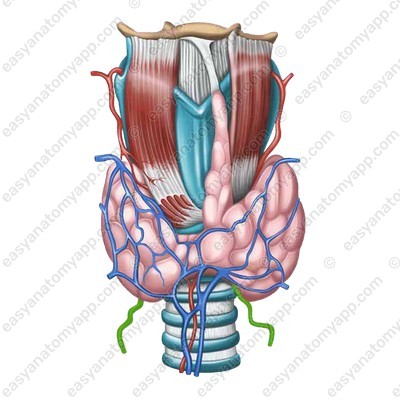

Иллюстрации и схемы по остеопорозу и паращитовидной железе